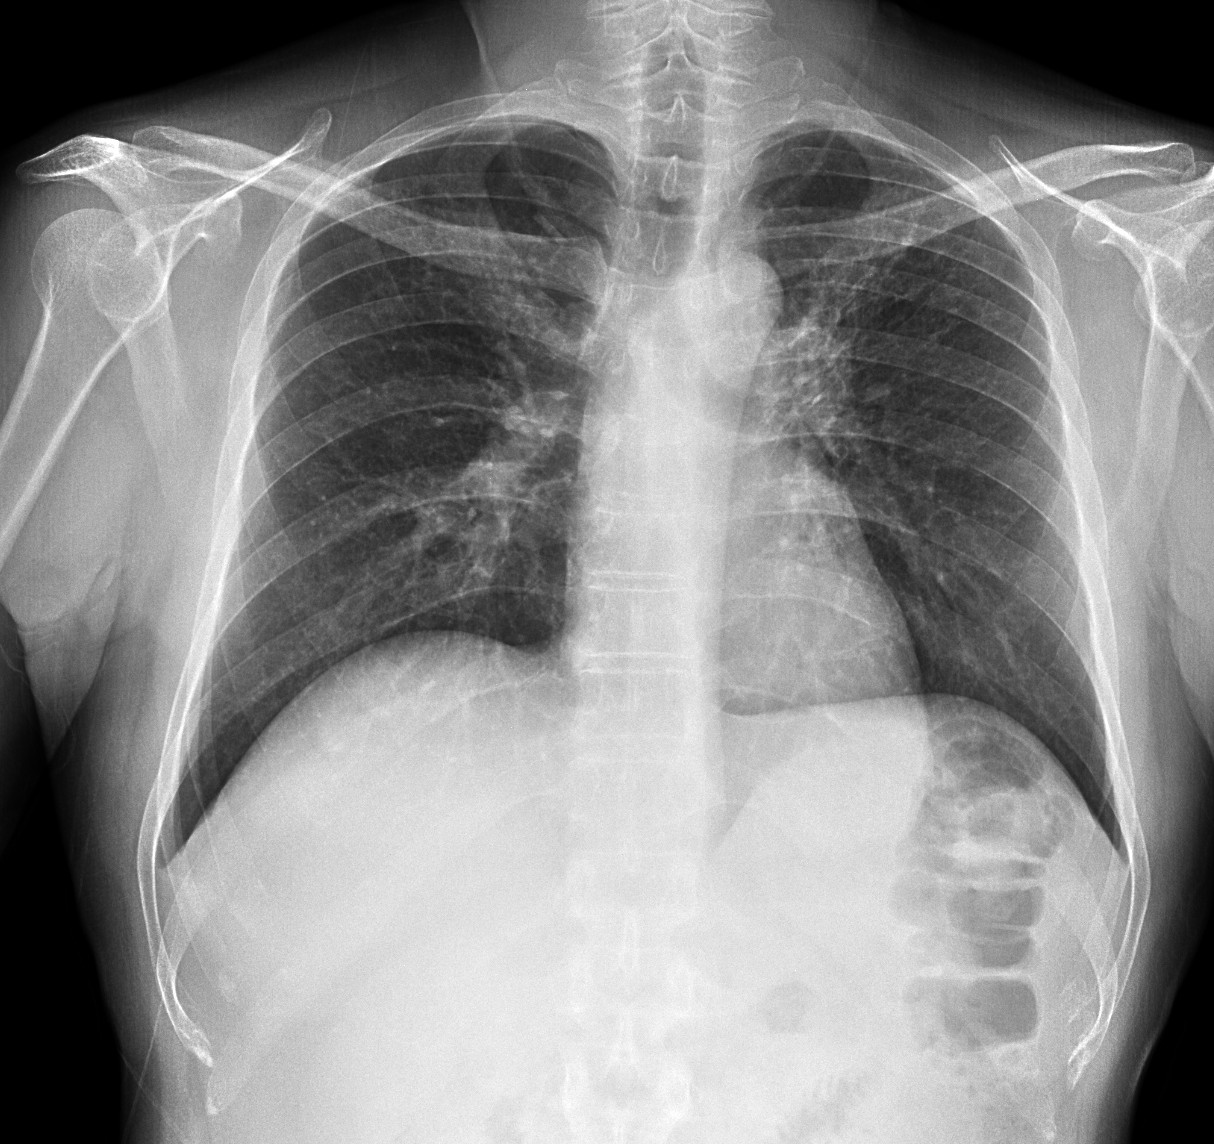

Se realiza placa de tórax, donde observamos:

Estos hallazgos descritos al pie de las radiografías son inespecíficos, pero al tratarse de un paciente inmunodeprimido, la primera posibilidad diagnóstica es una neumonía por Pneumocistis.

Radiografía: Inespecífica, 90% patológicas. Hasta 15% normales. Opacidades focales o en vidrio deslustrado, Infiltrado reticular intesticial, Neumatoceles, distribución perihiliar frecuente.